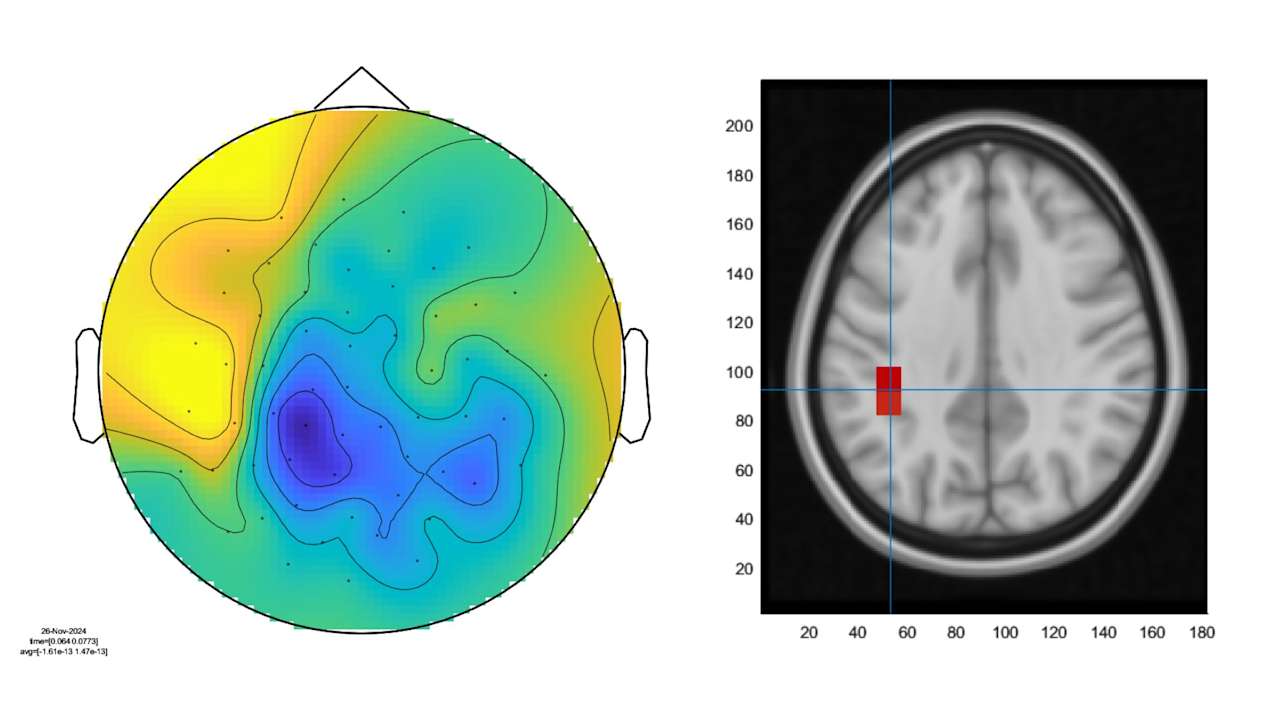

The OPM-MEG system uses quantum technology to monitor the electrical signals passed around the brain. Inside each sensor is a gas of atoms whose magnetic properties have been altered by a laser. Magnetic fields from our brain’s activity changes how the atoms move and by measuring that scientists can monitor brain activity.

In another test, I hold two fingers onto braille sensors which tingle when activated. The data is then analysed by Dr Karen Mullinger and her team.

“As the stimulus came on, the signal reduces,” she told me while pointing out fluctuations in brain activity on a graph.

“As the vibration on your finger stopped then we get this massive jump back up. What we see in patients with different neurological diseases is differences in this response.”

Had I suffered a concussion the line wouldn’t peak as high. In MS sufferers it recovers at a shallower gradient.